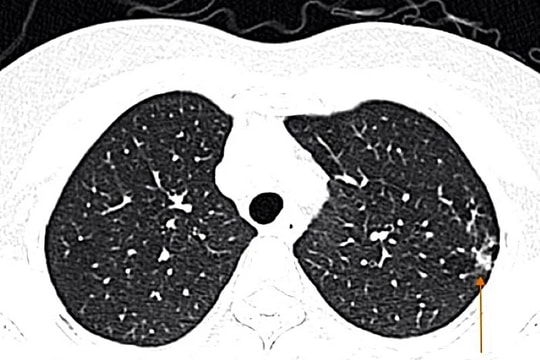

Khoa Cấp cứu, Bệnh viện Bệnh Nhiệt đới Trung ương đang điều trị cho gần 20 bệnh nhân viêm phổi, trong đó có những ca bệnh nặng, phải thở máy và lọc máu liên tục.